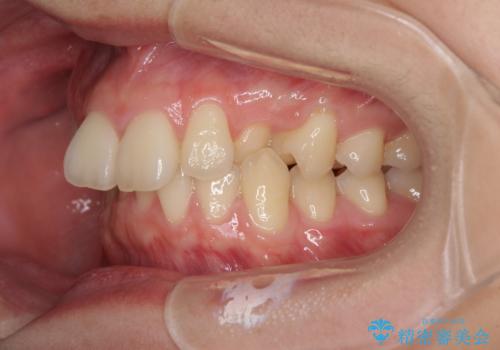

- 咬み合わせが悪いとのことで来院された患者様です。

ぱっと見はインビザラインによる矯正治療も可能と思われましたが、歯根が最も長い犬歯がクロスバイトになっており、インビザラインでは対応困難と判断され、ワイヤー装置にて矯正治療を行うこととしました。

クロスバイトになっている犬歯は、歯の移動に伴い装置を張り替えていくことで対応することとしました。